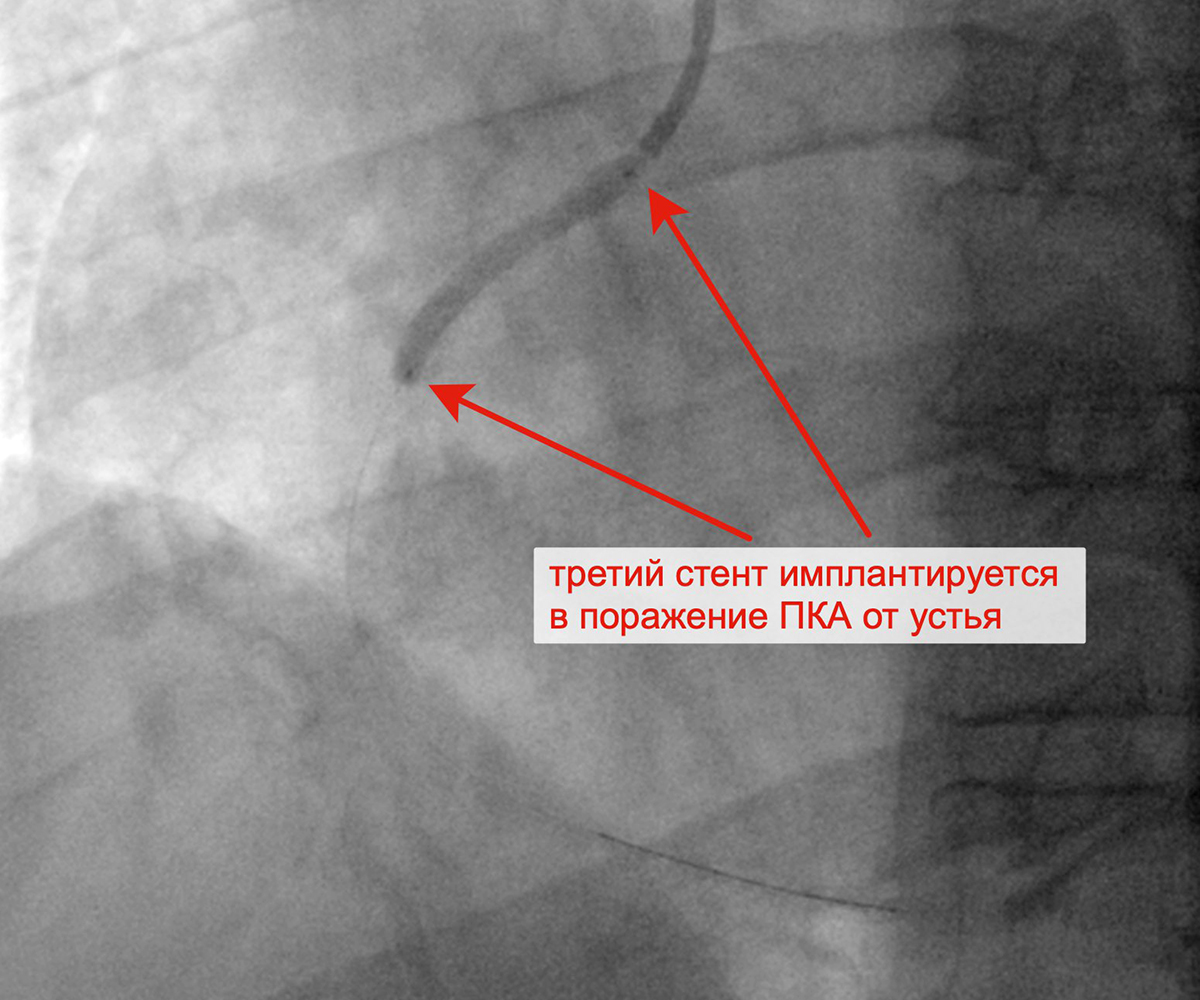

Чрескожное коронарное вмешательство (ЧКВ) на хронической окклюзии ПКА выполнялось билатеральным лучевым доступом: через левую лучевую артерию диагностическим катетером параллельно выполнялись съемки ЛКА, что позволило визуализировать через межсистемные коллатерали дистальное русло постокклюзированной ЗМЖА и контролировать процесс реканализации хронической окклюзии и проведение коронарного проводника в дистальное русло ЗМЖА. Успешно была выполнена реканализация ЗМЖА, баллонная ангиопластика и стентирование правой коронарной артерии (3 стента с лекарственным покрытием). При контрольной ангиографии: стенты и ПКА проходимы, позиционирование стентов адекватное, диссекции или остаточного стеноза в стентированных сегментах ПКА нет, кровоток TIMI 3 по ПКА и всем ветвям. Пациент был на следующий день выписан из клиники.

Имплантация третьего стента в ПКА от устья артерии Финальный результат реканализации, баллонной

ангиопластики и стентирования ПКА тремя стентами